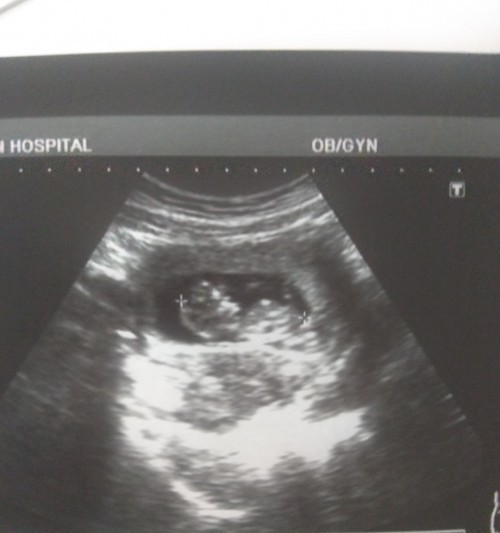

บ้านนี้9w1dก็เจอน้องแล้วนะคะ

บ้านนี้เจอน้องตอน8wค่ะ